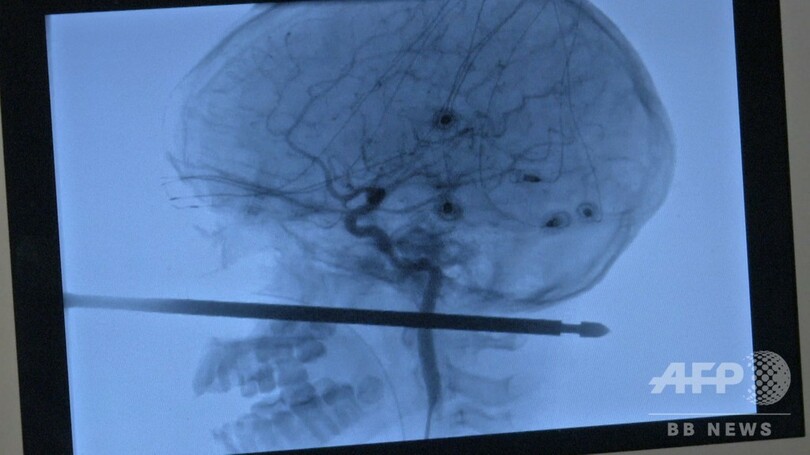

ゼイビア君は9日、隣接するカンザス州の病院で、左の頬から首の後ろまで突き刺さり、後頭部へ貫通する寸前で止まった長い金串を除去する手術を受けた。順調な回復を見せているという。

大学病院の神経外科医、コージ・エバーソール(Koji Ebersole)氏は、地元紙カンザスシティー・スター(Kansas City Star)に、金串は「目、脳、脊髄の全てをそれて」刺さっていたと語った。「顔面から後頭部まで5~6インチ(約13~15センチ)もの物体が突き抜けたのに、これらの部位を傷つけなかったというのは、100万人に1人の症例だ」

エバーソール医師によれば、金串が刺さった部位の周囲には重要な血管が多かったが、大きな出血はなかったため、翌朝まで時間をかけて慎重に手術の準備を進めることができた。手術には約100人の医療関係者が参加したという。(c)AFP/Nova SAFO